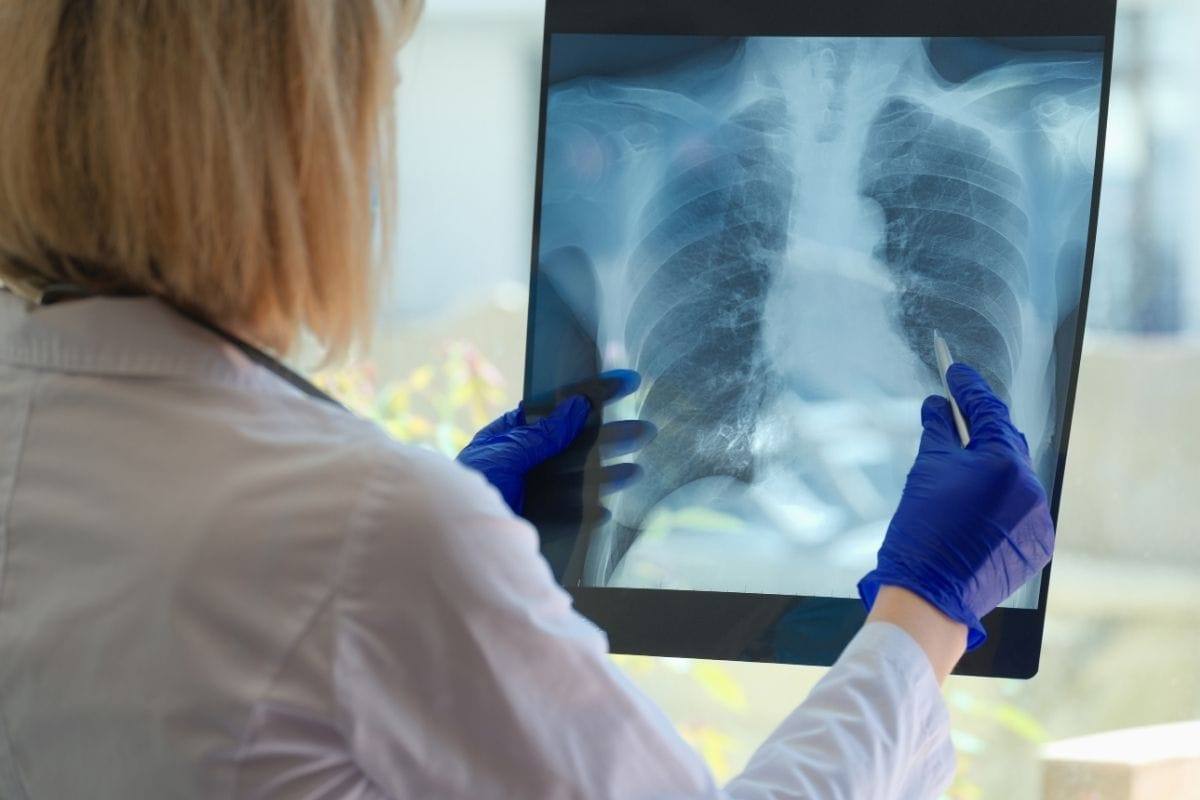

Recognizing Pathological Changes

When checking a chest X-ray for bronchitis, we look for signs that are not normal. Bronchial wall thickening and increased interstitial markings are common in bronchitis. These signs show inflammation and infection in the bronchial tubes.

Spotting these changes is essential for diagnosing bronchitis and telling it apart from other lung issues.

Key Bronchitis CXR Finding #2: Increased Interstitial Markings

Increased interstitial markings on a chest X-ray are key signs of bronchitis. They show peribronchial inflammation. This happens when the bronchi and surrounding tissues get inflamed.

Identifying Peribronchial Inflammation

On chest X-rays, peribronchial inflammation shows as increased interstitial markings. These markings look like linear or reticular patterns around the bronchi. The inflammation makes the bronchial walls thicker and more visible.

Distinguishing Features

The signs of increased interstitial markings include peribronchial distribution and tram-track signs or cuffing around the bronchi. These signs show that the bronchial walls are thickening.